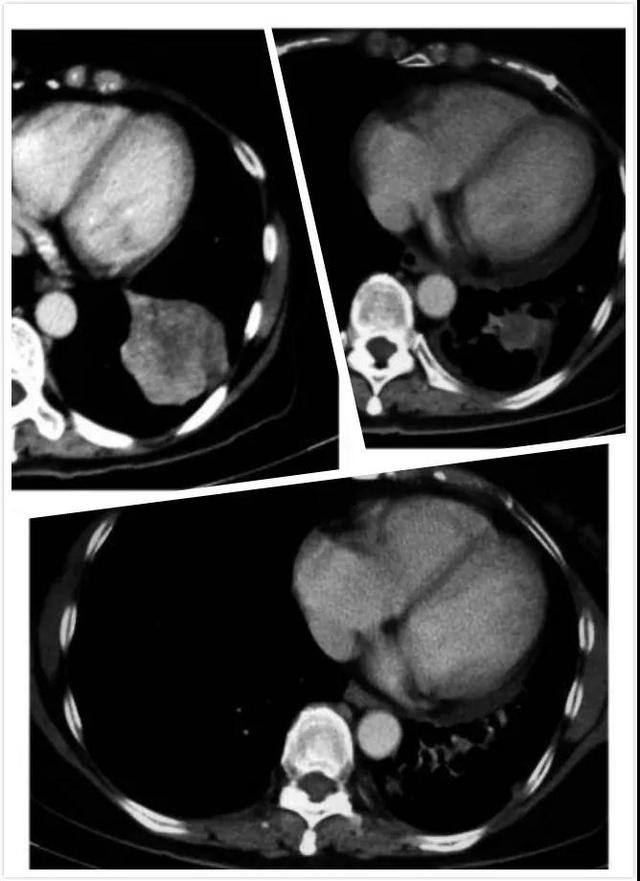

我于2007年12月被诊断患有T4N1M0-IIIb期NSCLC,当时54岁,病灶为9厘米×5.8厘米×7.2厘米。我在3个月内接受3次紫杉醇(260 mg)和卡铂(415 mg)治疗。肿瘤减小到7cm×6cm×5cm,同时放化疗,两个月后,我申请参加非小细胞肺癌疫苗方案。治疗前下肺叶病变为3厘米×3厘米(图1),3个月后,肿瘤缩小到2cm×2.1cm(图2)。FNM女士在治疗过程中没有报告任何副作用。在停药后3个月(18个月)进行CT胸部扫描,肿瘤大小“无明显变化”(图3)。最后一次随访 - 停止疫苗后28个月 - FNM女士身体健康,她的ECOG状态一直保持在0.